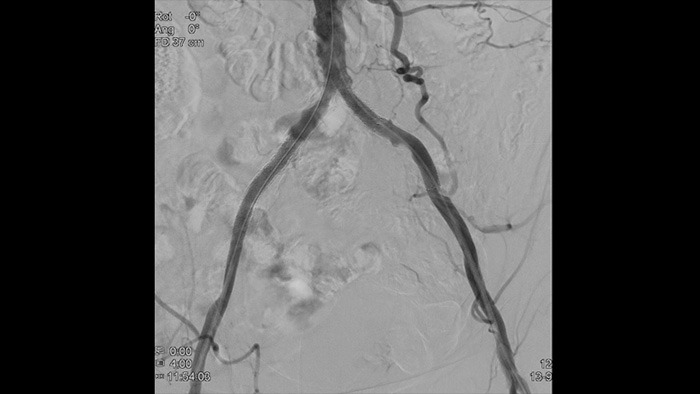

Внутрисосудистое ультразвуковое исследование (ВСУЗИ) — это технология визуализации с использованием катетера, которая позволяет визуализировать кровеносные сосуды изнутри и помогает определить наличие и степень заболевания. С помощью ВСУЗИ можно подобрать и осуществить подходящую медицинскую процедуру индивидуально для каждого пациента, а также убедиться в успешности лечения.

Создает изображения высокого разрешения, позволяя детально рассмотреть сосуды и таким образом обеспечивая проведение точного курса лечения, навигации и последующего наблюдения за пациентом.